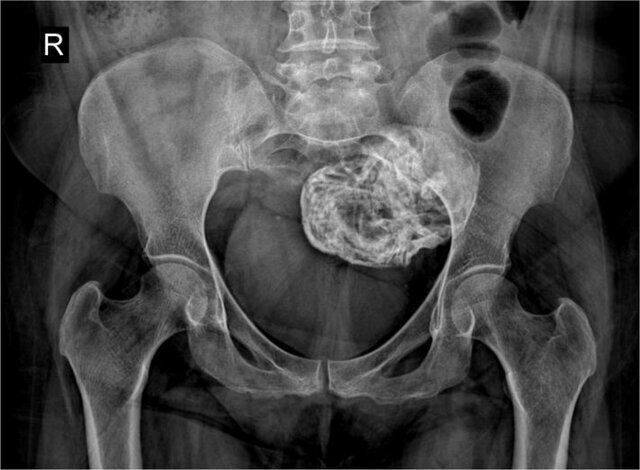

عضو گروه رادیولوژی بیمارستان شهید ستاری دانشگاه علوم پزشکی شهید بهشتی در مورد خارج کردن جنین سنگی از یک خانم ۵۲ ساله در ایران توضیح داد: در این مورد که اخیراً گزارش شده است، یک بیمار ۵۲ ساله به دنبال تصادف، به اورژانس مراجعه میکند. با یک عکس ساده لگن پزشکان متوجه وجود یک توده در بدن فرد میشوند و توده از طریق جراحی از بدن فرد خارج میشود. بر اساس بررسیهای انجامشده، مشخص میشود که این توده «لیتوپدیون» یا جنین سنگی است.

«لیتوپدیون» یا جنین سنگی یکی از عوارض بسیار نادر حاملگیهای خارج رحمی است که به صورت توده کلسیفیه در قسمتی از حفره شکم یا لگن ظاهر میشود. کلسیمی شدن یا کلسیفیکاسیون رسوب کلسیم در بافتی از بدن است.

در لیتوپدیون یا جنین سنگی، پس از لقاح، جنین خارج از رحم تشکیل میشود، ولی به دلیل اینکه شرایط برای رشد آن مناسب نیست، پس از مدتی رشد متوقف میشود و شروع به کلسیمی شدن میکند. معمولاً فرد از وجود جنین سنگی در بدن خود مطلع نمیشود و سالها بعد به صورت اتفاقی وجود آن مشخص میشود.